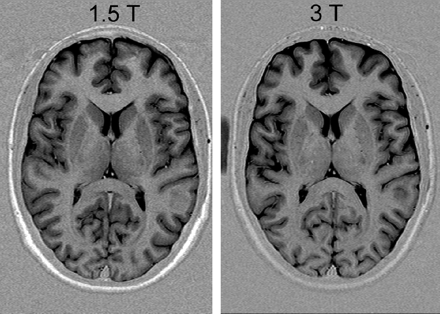

Apparently, gray-to-white matter contrast is reduced in spin-echo T1 imaging at 3T (30) when compared with 1.5T (Fig 6). There are several factors contributing to this observation. T1 times of gray and white matter lengthen and converge at higher fields (31–33). Moreover, shielding effects induced by eddy currents prevent central parts of the image from being properly excited (16), which results in reduced signal intensity of the basal ganglia region. In addition, magnetization transfer effects are enhanced at higher B0, thus reducing signal intensity and contrast. There are several ways to compensate for these effects. For example, inversion recovery sequences appear very well suited if one is only interested in increasing gray to white matter contrast (Fig 7). The inversion pulse, however, interferes with visualization of contrast enhancement following gadolinium administration. Enhancing lesions may not be visible (Fig 8), because in inversion recovery sequences, unlike conventional T1 spin-echo sequences, the tissue with the shortest T1 does not necessarily exhibit the brightest signal intensity, depending on T1. Therefore, inversion recovery sequences are not quite useful for comparative pre- and postcontrast T1 spin-echo imaging, regardless of B0. A different approach to increase gray-to-white matter contrast during T1-weighted spin-echo imaging at both field strengths is to reduce the excitation flip angle (34). Although this reduces SNR slightly, the gain in gray-to-white matter contrast is obvious and more pronounced at 3T (Fig 9). The effect can be predicted from theoretical calculations (35) by using known T1 and T2 relaxation times of gray and white matter (33) but is empirically larger than the theoretical predictions at 3T, probably because of shielding and magnetization transfer effects (34).

Left, T1 spin-echo image at 1.5T (TR, 600 ms; TE, 14 ms; bandwidth, 90 Hz/pixel; section thickness, 5 mm; matrix, 256 × 192; FOV, 220 × 220 mm2; flip angle, 90°). Right, T1 spin-echo at 3T (TR, 700 ms; TE, 10 ms; section thickness, 5 mm; 19 sections; bandwidth, 200 Hz/pixel; matrix, 256 × 192; FOV, 220 × 220 mm2; flip angle, 90°), which is indicative of the reduced gray-to-white matter contrast at higher fields.